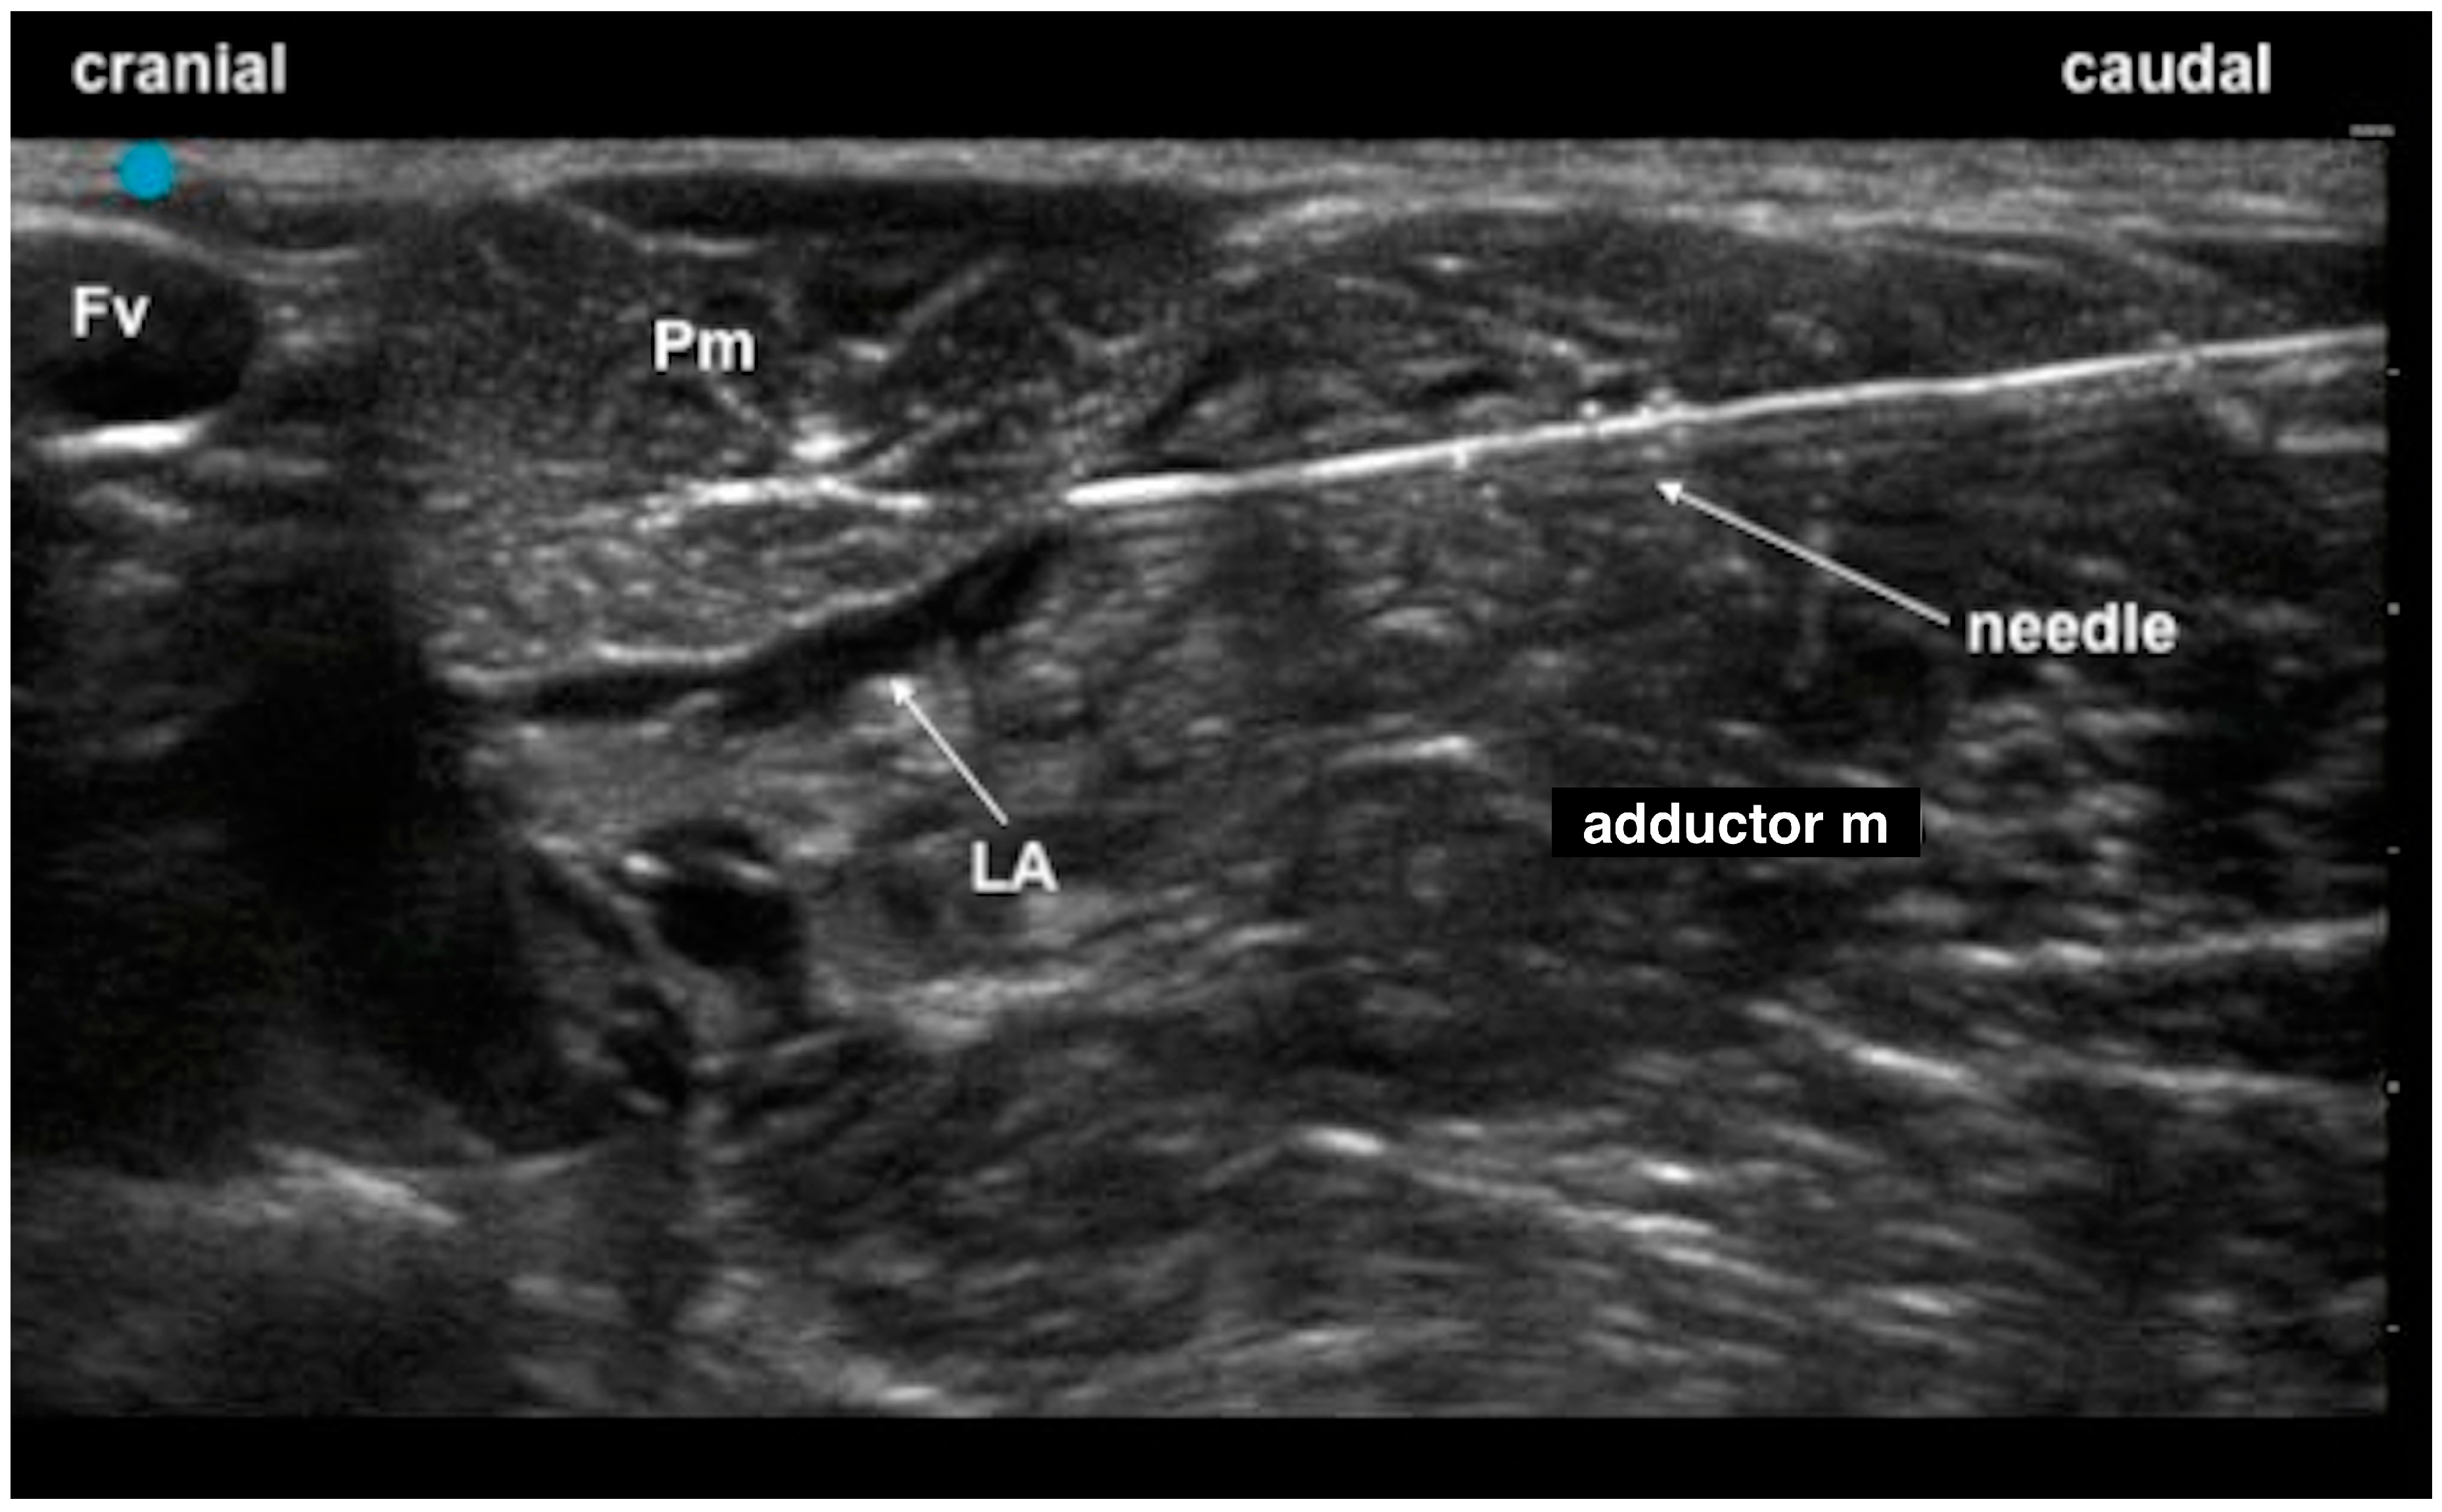

2.1. Phase 1: Anatomical Study

- Castro, D.S.; Garcia-Pereira, F.; Giglio, R.F. Evaluation of the potential efficacy of an ultrasound-guided adductor canal block technique in dog cadavers. Vet. Anaesth. Analg. 2018, 45, 566–574. [Google Scholar] [CrossRef] [PubMed]

- Di Franco, C.; Tayari, H.; Nardi, S.; Briganti, A. Along or across the visual axis: A comparison of two ultrasound screen, needle and transducer orientation techniques. Vet. Anaesth. Analg. 2021, 48, 147–150. [Google Scholar] [CrossRef] [PubMed]